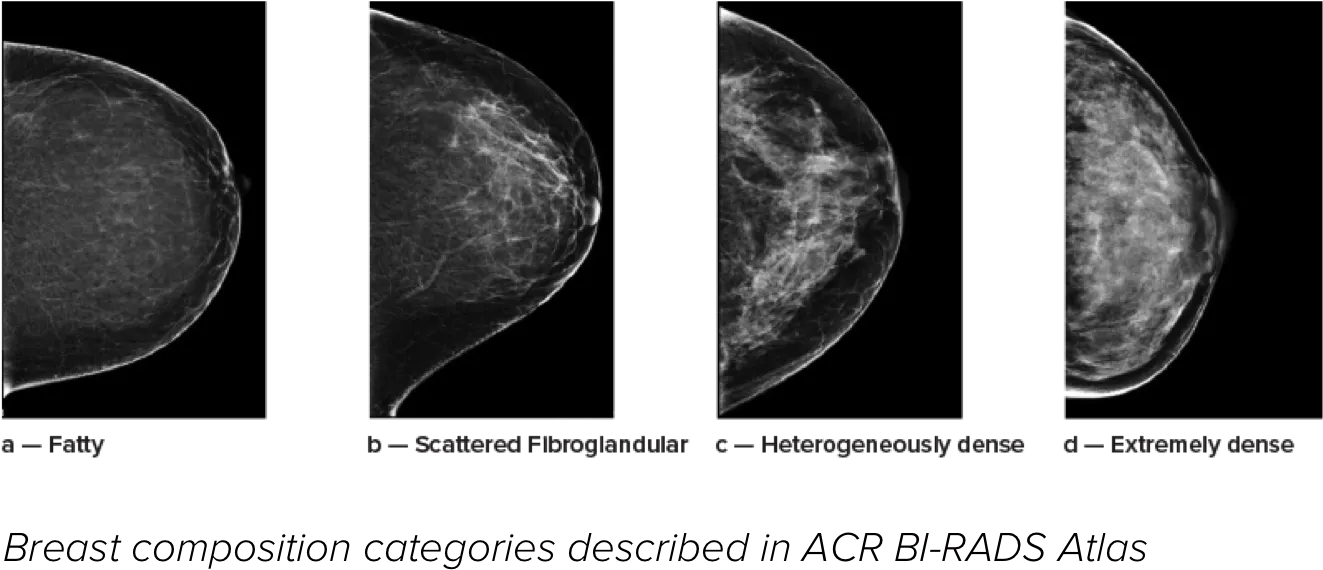

Higher breast density is known to increase a woman’s risk for breast cancer.1 The need for accurate, unbiased analysis is therefore critical. Powered by machine learning, Quantra technology software analyses both 2D™ and tomosynthesis images for distribution and texture of parenchymal tissue. It categorises breasts in four breast composition categories consistent with guidance from the American College of Radiology (ACR) BI-RADS Atlas 5th Edition.2

Breast composition categories as described in ACR BI-RADS Atlas.